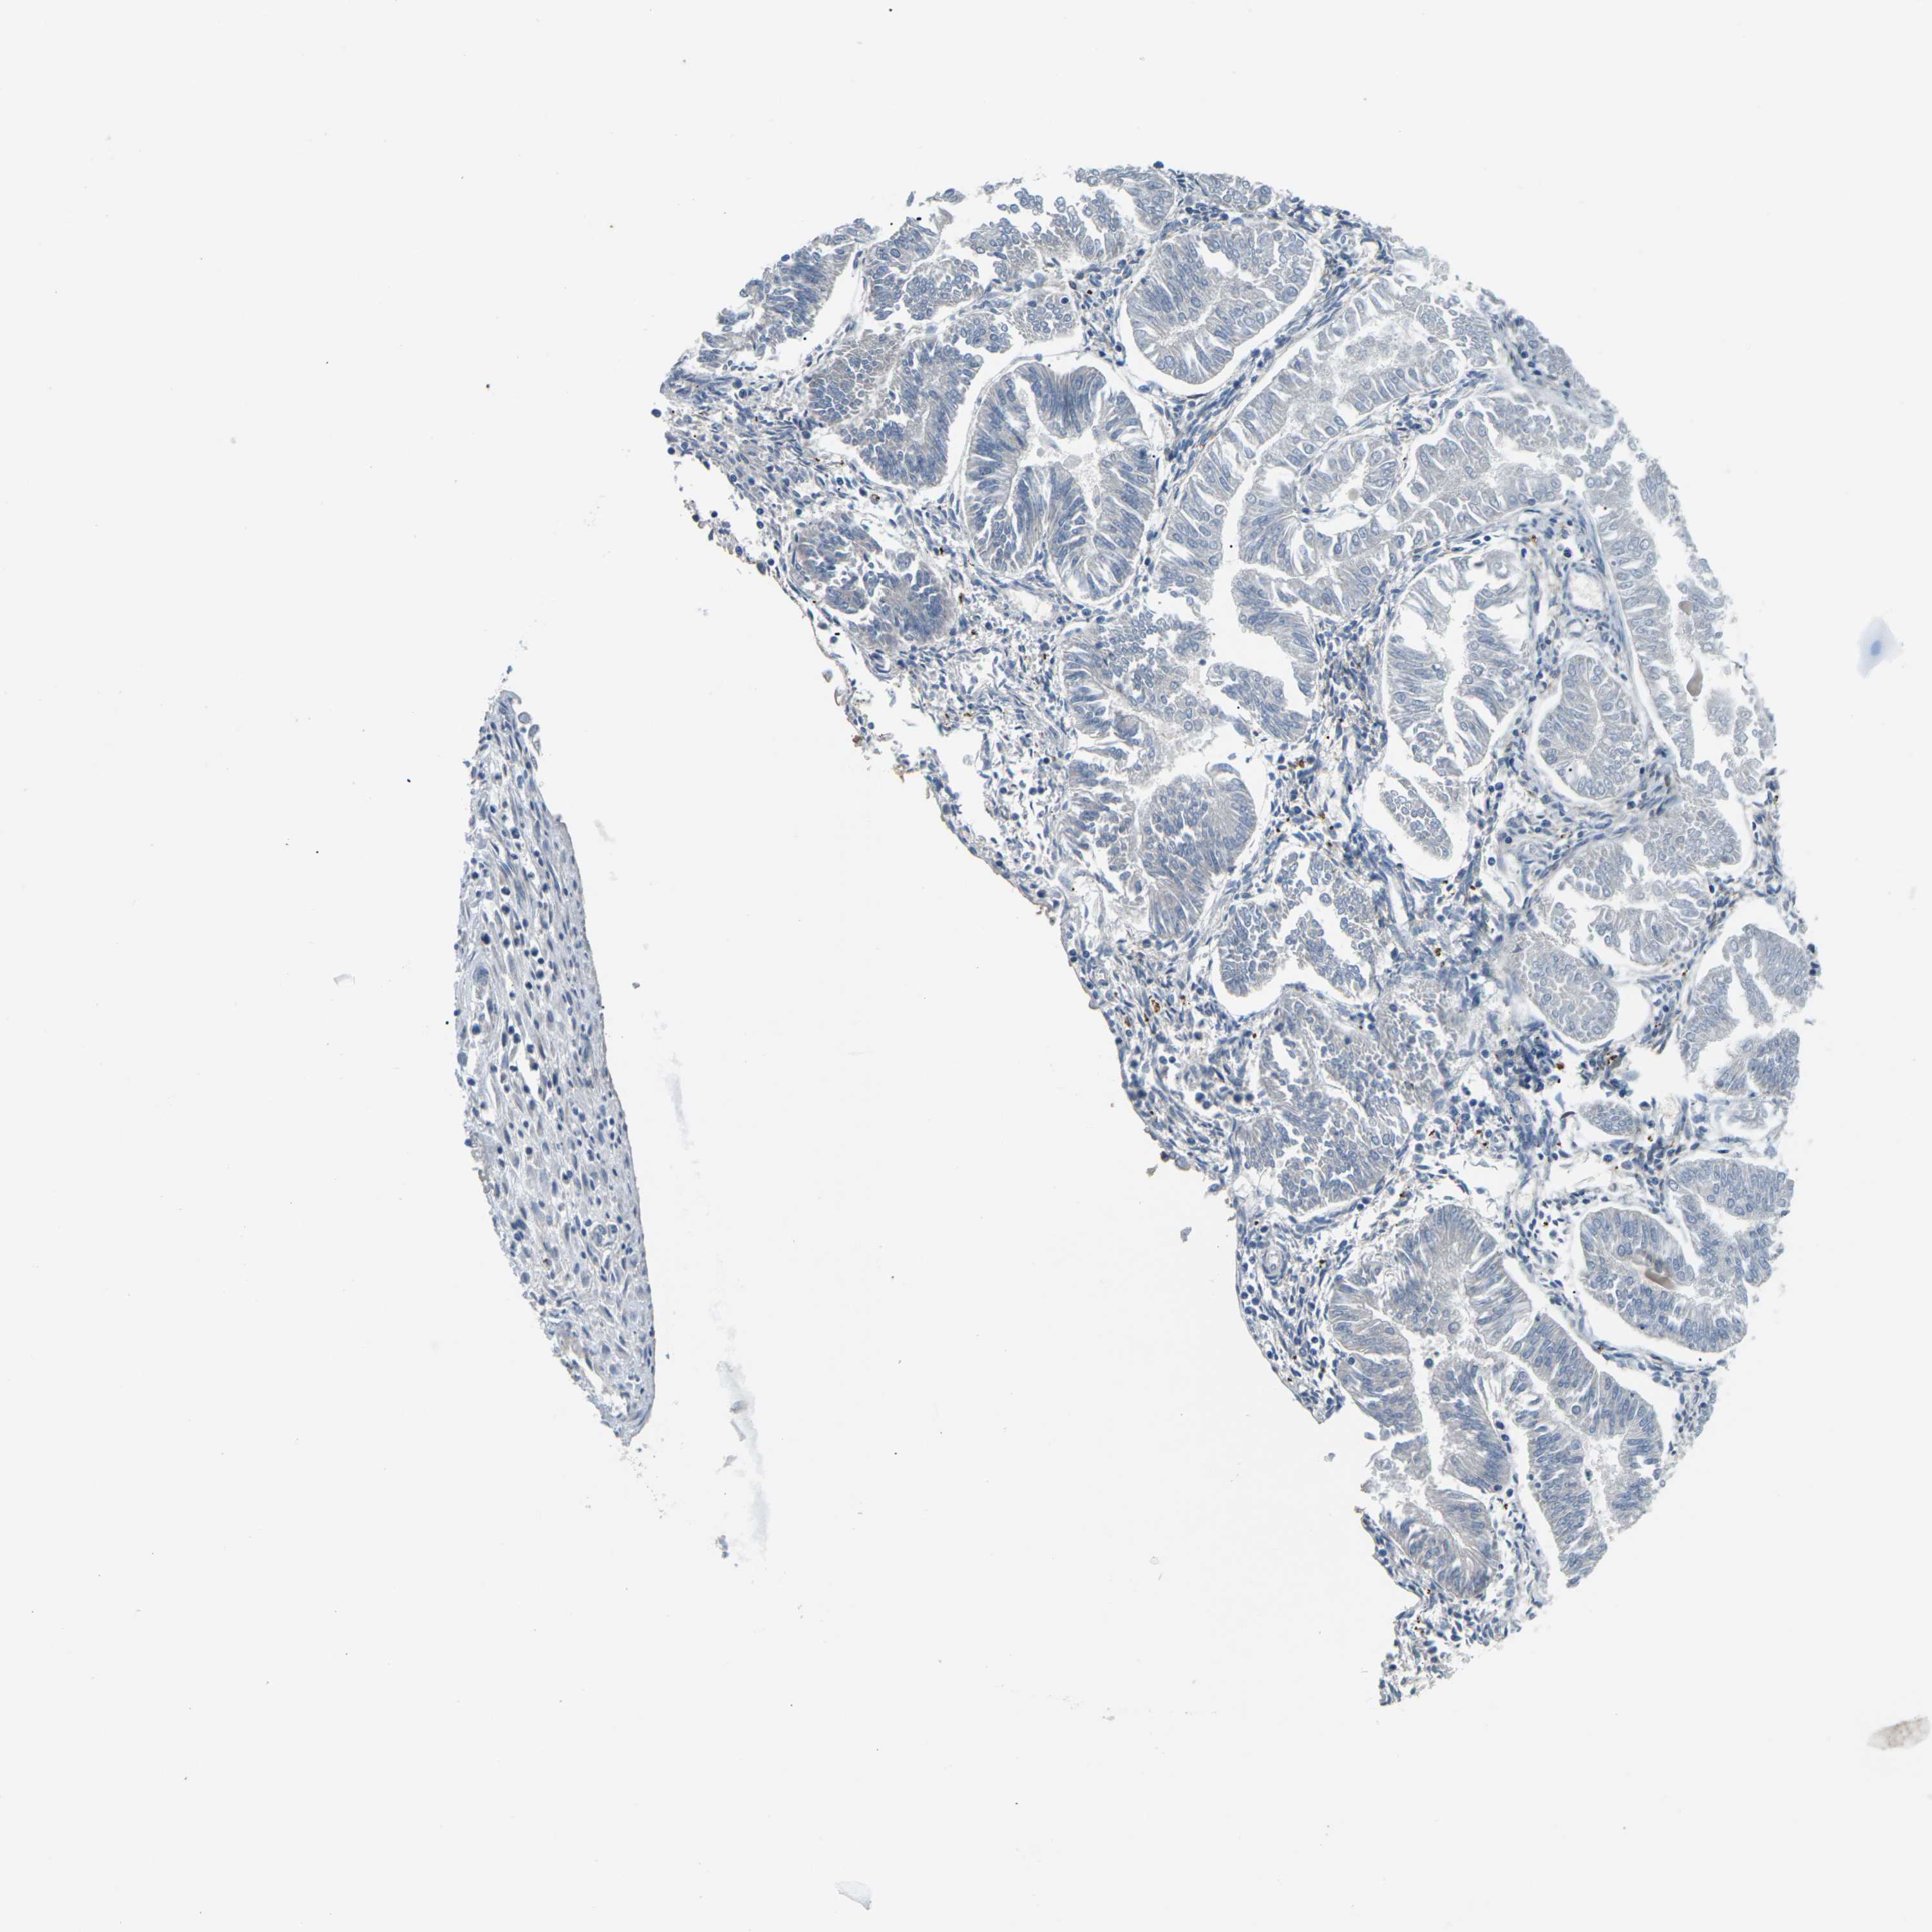

ENDOMETRIAL CANCER - Protein expressioni

A mouse-over function shows sample information and annotation data. Click on an image to view it in a full screen mode. Samples can be filtered based on level of antibody staining by selecting one or several of the following categories: high, medium, low and not detected. The assay and annotation is described here.

Note that samples used for immunohistochemistry by the Human Protein Atlas do not correspond to samples in the TCGA dataset.

Antibody stainingi

Antibody staining in the annotated cell types in the current human tissue is reported as not detected, low, medium, or high, based on conventional immunohistochemistry profiling in selected tissues. This score is based on the combination of the staining intensity and fraction of stained cells.

Each image is clickable and will lead to virtual microscopy that enables deeper exploration of all samples and also displays staining intensity scores, fraction scores and subcellular localization as well as patient and tissue information for each sample.

Antibody HPA014353

Antibody HPA014736

Staining

High

Medium

Low

Not detected

Intensity

Strong

Moderate

Weak

Negative

Quantity

>75%

75%-25%

<25%

None

Location

Nuclear

Cytoplasmic/membranous

Cytoplasmic/membranous,nuclear

Adenocarcinoma, NOS